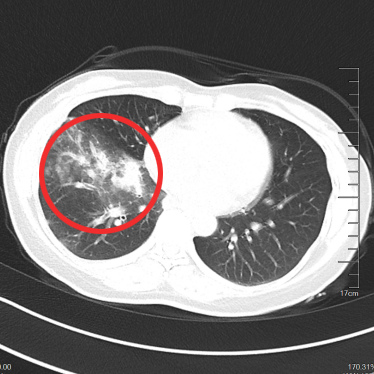

▲治疗后2年半

▲治疗前

▲治疗后1月